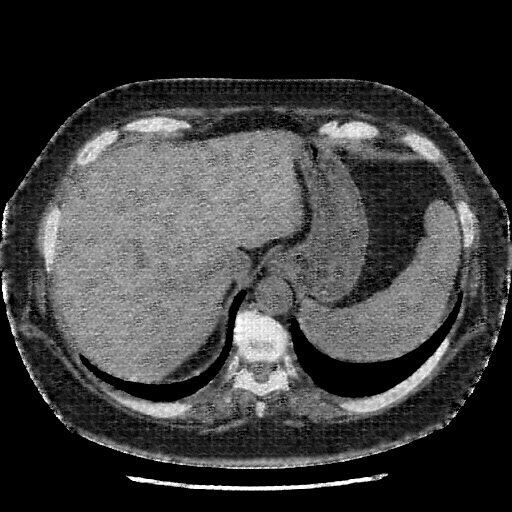

Original VENOUS CT scan

Full window (WL 1023.5, WW 4095 β†’ Low βˆ’1024, High +3071)

Generated VENOUS CT scan (A→B translation)